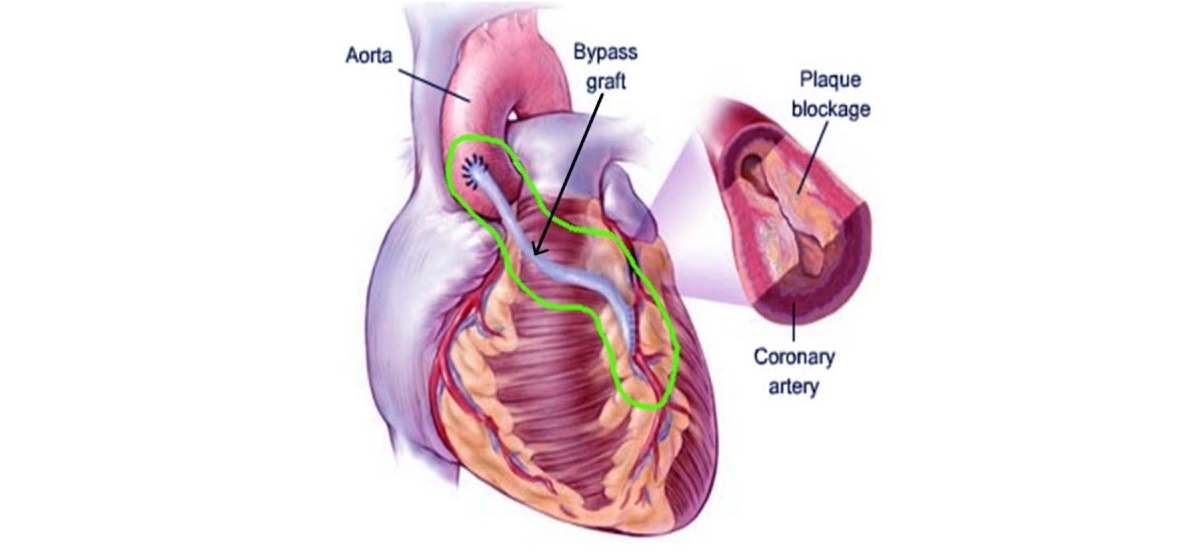

Overview

Package includes:

Days in hospital : 7 to 8 Days (For patient and one attendant)

Days in hotel : 12 Days (For patient and one attendant)

Room type in hospital : Shared

Room type in hotel : Private

Hotel category: Standard

Value added benefits of the CABG: